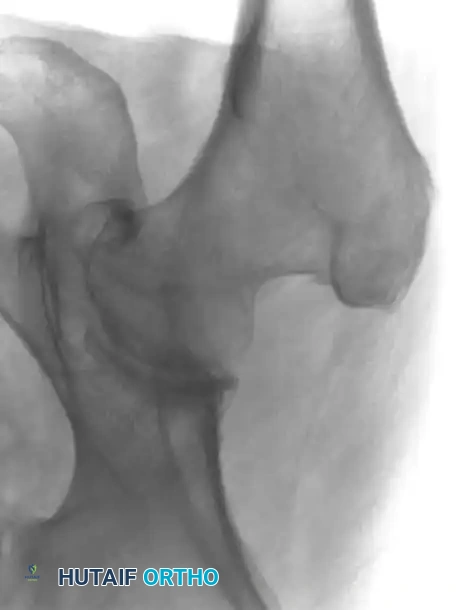

لا تقتصر قوة الرنين المغناطيسي على مفصل الورك فحسب، بل تمتد لتشمل المفاصل الأخرى كالركبة، مما يثبت فعالية هذه التقنية في كشف أدق التفاصيل التشريحية والمرضية في العظام والغضاريف. نستعرض هنا بعض الأمثلة التي توضح دقة الرنين المغناطيسي في تشخيص إصابات المفاصل:

هذه الصور تؤكد بما لا يدع مجالا للشك أن الاعتماد على الرنين المغناطيسي يوفر خريطة طريق واضحة للطبيب المعالج، سواء كان يتعامل مع كيس زلالي، أو كدمة عظمية، أو كسر خفي في صفيحة النمو، أو آفة غضروفية، مما ينعكس إيجابا على دقة التشخيص في مفصل الورك والمفاصل الأخرى.